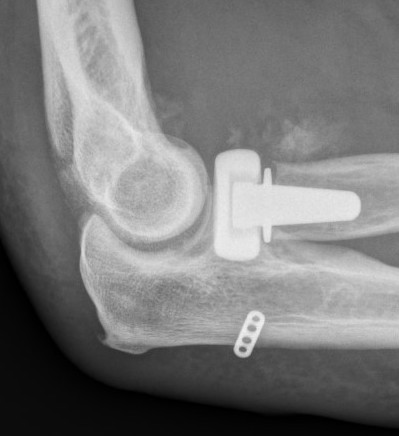

Radial head replacement with lag screw fixation of Type II coronoid

Radial head replacement with lasso fixation of small coronoid fragment

2. Restore radial head stability - radial head ORIF or arthroplasty

3. Restore lateral stability - LCL repair and common extensor origin +/- reconstruct +/- internal brace